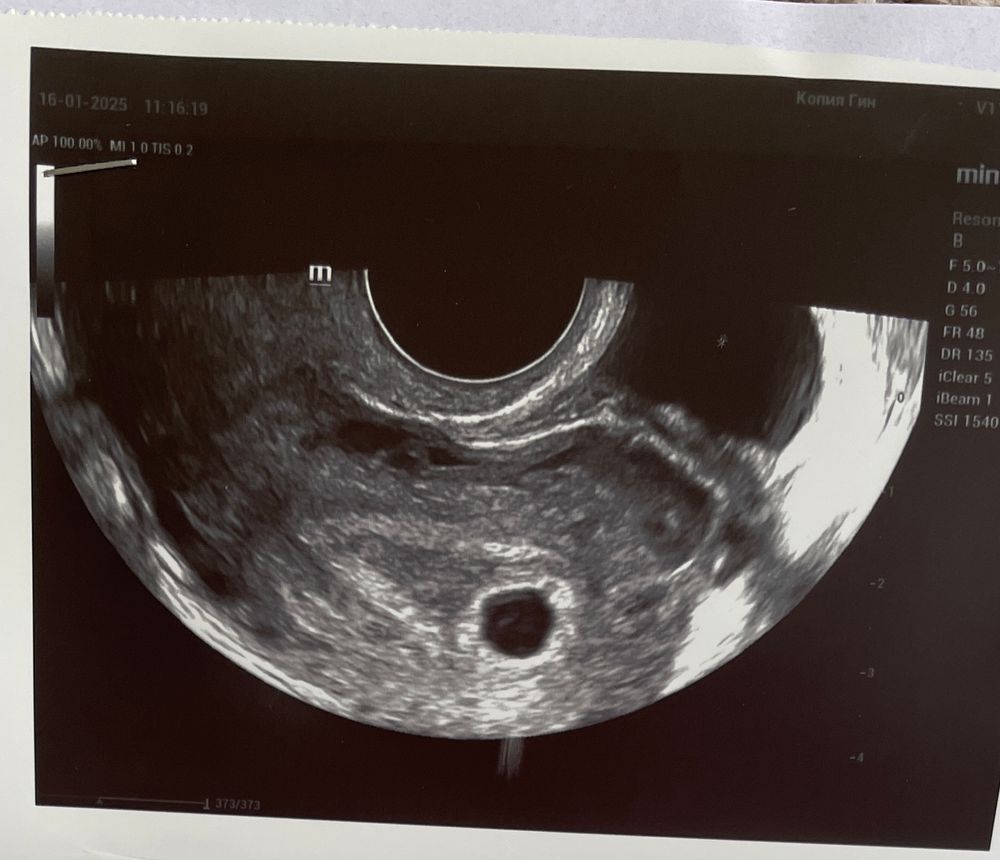

Ирина, нет, не было. Прикрепляю узи снимок Изображение